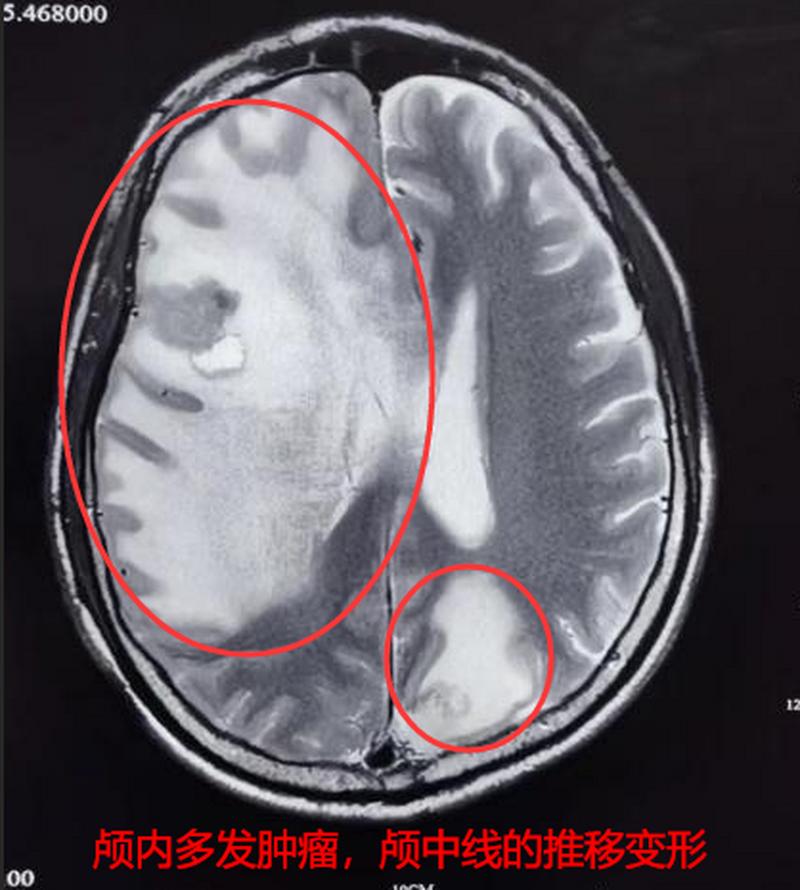

肺腺癌晚期脑转移(癌症问题):

- 本质:这是癌细胞从肺部通过血液循环转移到了大脑,形成了新的肿瘤(转移灶),这是癌症的晚期表现,意味着癌细胞已经扩散到全身。

- 占位效应:脑瘤会像“占道施工”一样,挤压周围的正常脑组织,导致颅内压增高,引起头痛、呕吐、视力模糊等症状。

- 神经功能损伤:根据脑瘤位置不同,会破坏控制运动、语言、感觉等功能的神经通路,导致偏瘫、失语、癫痫等。

- 癌症进展:如果不加控制,脑瘤会继续生长,导致病情迅速恶化。